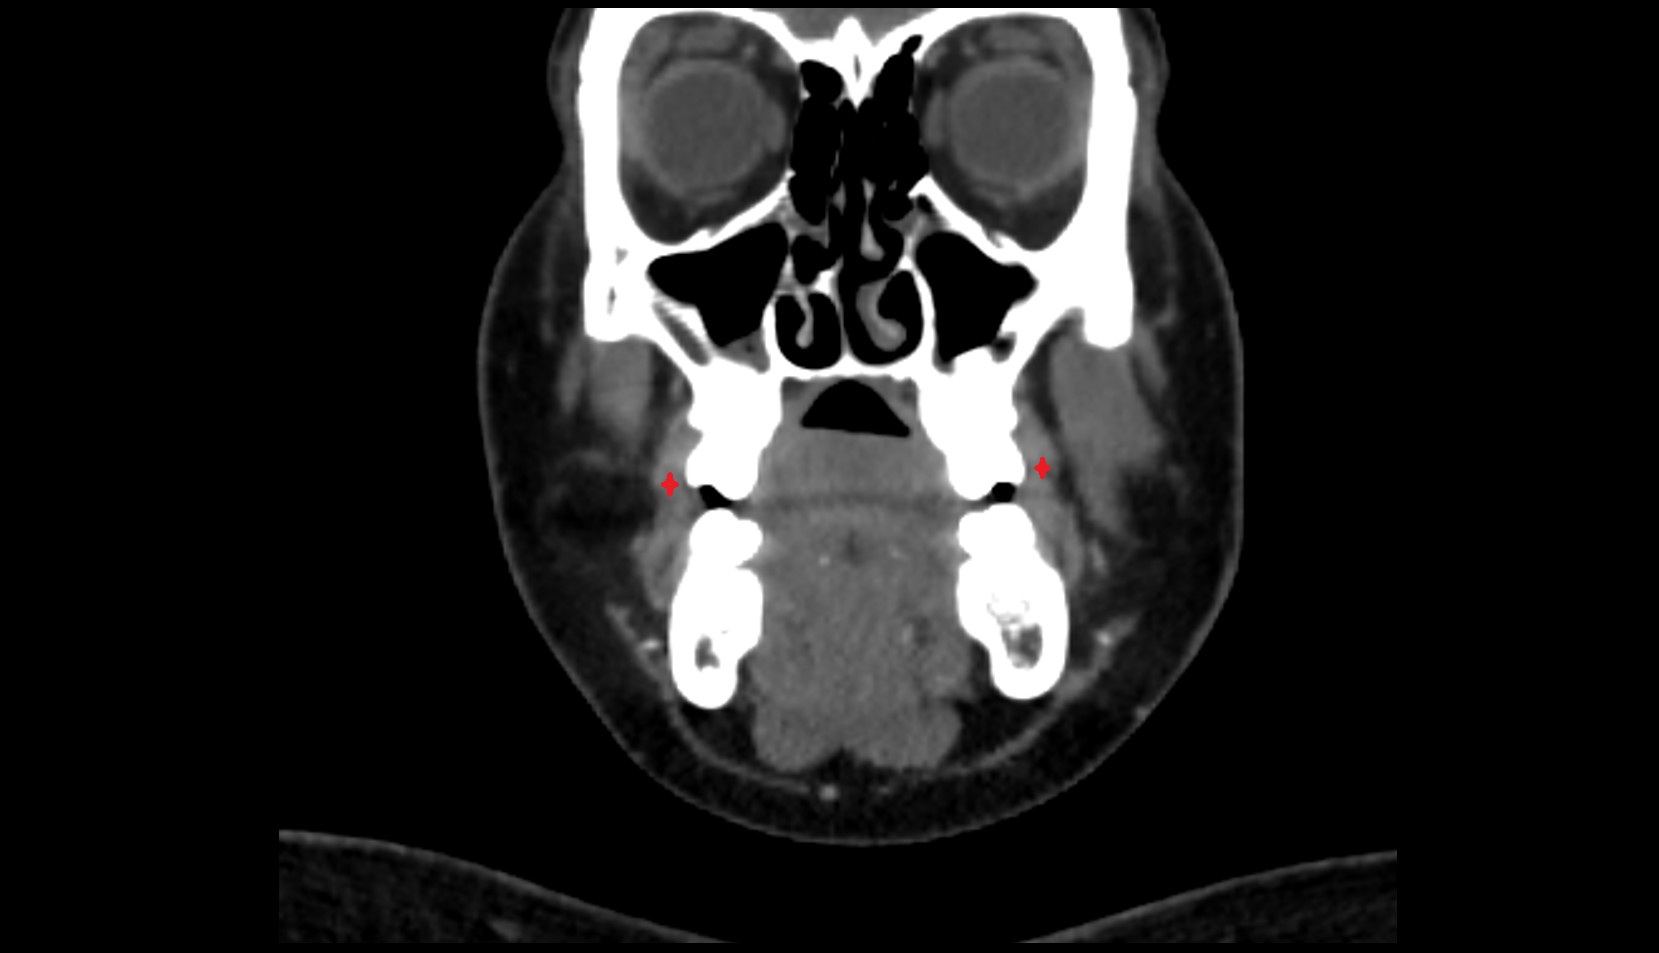

- Temporomandibular joint

- Mandibular condyle

- Mandibular fossa